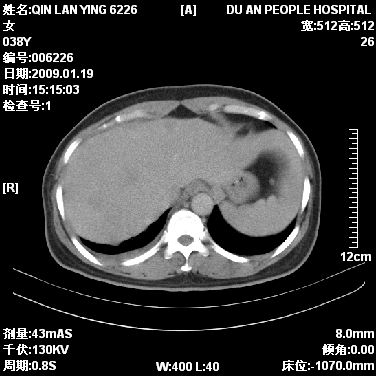

女,38岁,胸疼1个月。wbc:1万4

1)右肺中央型肺癌并右肺上叶阻塞性肺炎、节段性肺不张,纵隔淋巴结转移、右侧胸膜转移、肝脏转移。2)右侧胸腔少量积液。

1、右侧中央型肺癌并阻塞性肺不张,纵隔内、主动脉弓旁、右肺门淋巴结及肝脏转移可能性大,建议纤支镜进一步检查。

2、右侧胸腔积液。

本病例有几个容易诊断的地方:1、右肺上叶前段支气管闭塞,肺不张。2、淋巴结明显肿大。3、肝脏多个类圆形低密度影呈“牛眼征”改变,高度提示转移。

从影像学角度分析      右肺上叶中央型肺癌,并阻塞性不张、肺炎,纵隔淋巴结、膈顶淋巴结转移。

肝内两个大小不等低密度结节,内可见更低密度影,首先考虑肝内转移瘤,但联想到患者wbc1万4,建议楼主还是做个增强比较明确,除外肝脓肿的可能。